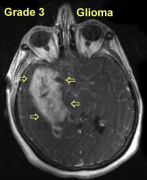

胶质瘤3~4级活多久? 胶质瘤是脑恶性肿瘤中常见的疾病。如果3-4级胶质瘤能早期发现并完全切除,存活的机会相对较长。如果达到3级或4级,一般来说,低...

胶质脑瘤存活率是多久? 胶质脑瘤的存活率是多久?神经胶质瘤是一种脑系统疾病。患者发病后,可根据四个不同等级了解生存时间。由于各级治疗方法不...

胶质脑瘤的存活率是多久? 胶质瘤是一种恶性颅内肿瘤,但其存活时间因肿瘤水平而异。一般来说,世卫组织的分级是四级。此外,还有一种类型。现在我...